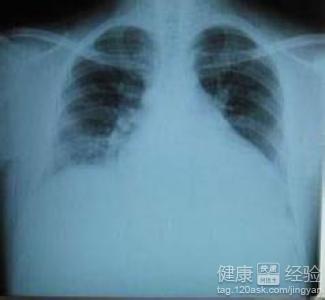

1該病多發生在懷孕前並沒有心髒病的女性人群中,一旦發病後,患者可以出現了呼吸困難或者是心理衰竭的情況發生。類似擴張型心肌病者稱為圍生期心肌病。可有心室擴大,附壁血栓。本病的特點之一是體循環或肺循環栓塞的出現頻率較高。